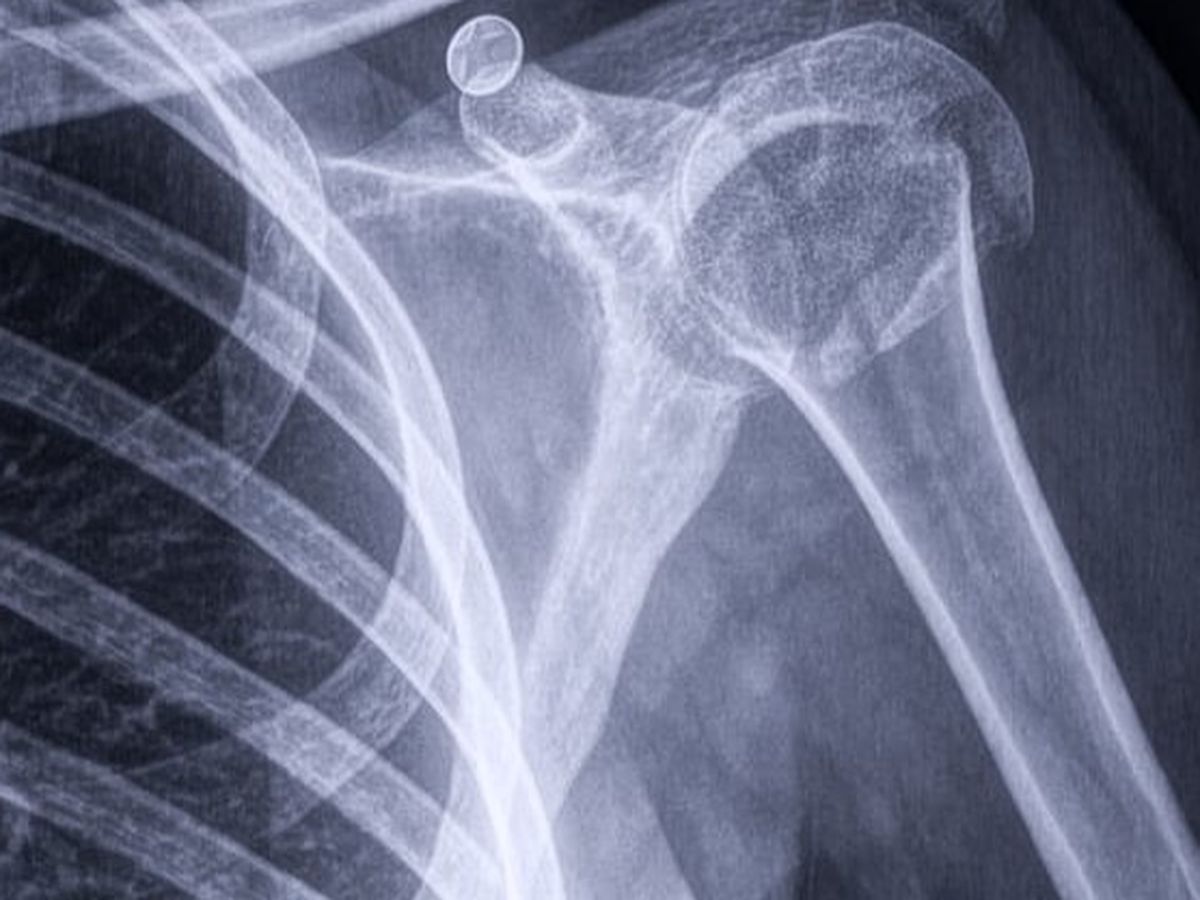

El pasado 3 de febrero, Daniela sufrió una caída que le provocó una fractura en el hombro. Tras varios estudios, se confirmó que necesita una operación urgente para no perder la movilidad de su brazo.

La cirugía está programada para el martes 17 de febrero a las 4:00 pm en el Hospital Diomed. Sin embargo, Daniela no cuenta con seguro de gastos médicos, y los costos de la operación, hospitalización y honorarios médicos son muy elevados.